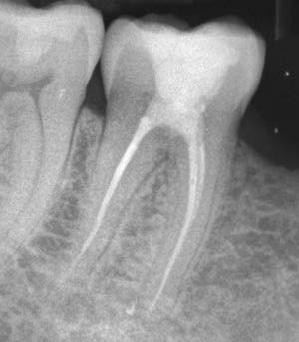

6. a–d. ábrák: A bal alsó második nagyőrlőfogon (3.7) kialakított konzervatív hozzáférési nyíláson keresztül végzett endodonciai kezelés lépései. A mezialis gyökér jelentős mértékben görbült. A gyökértömés hidraulikus kondenzációs technikával készült.

b. ábrák: A jobb alsó első nagyőrlőfogon (4.6) lévő cirkóniumkoronán keresztül elvégzett endodonciai kezelés. A hozzáférési nyílás kialakítása a lehető legkonzervatívabb módon történt. A gyökértömés hidraulikus kondenzációs technikával készült.